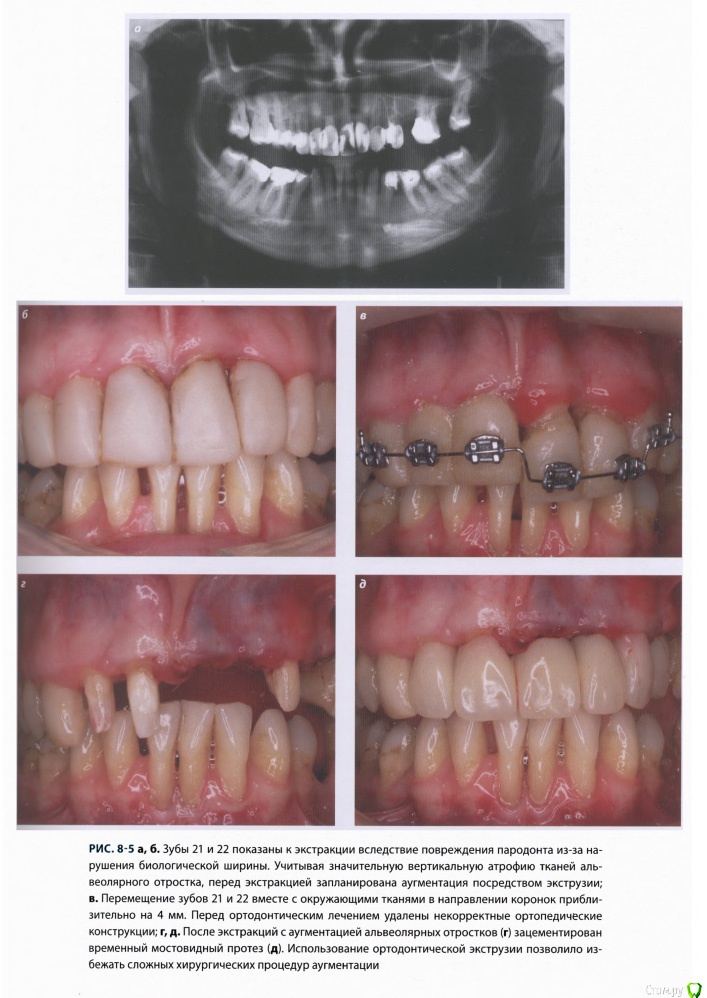

Romanson Опубликовано 25 июня, 2015 Поделиться Опубликовано 25 июня, 2015 Интересная тема, спасибо Колчанов за её создание. Вопрос такой - при ортоэкструзии обязательно нужно каждую неделю "подрезать" круговую связку? По теме есть вот такой кейс, автора к сожалению не помню. 2 Ссылка на комментарий

Romanson Опубликовано 25 июня, 2015 Поделиться Опубликовано 25 июня, 2015 И вот такой небольшой раздел из книжки 2011 года. Ссылка на комментарий